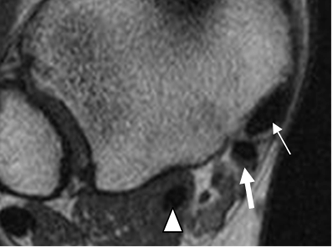

Fig 8. Ligamentos de la sindesmosis normal.

A y B: RM axial en T1. Ligamento tibioperoneo anterior (flecha delgada) y tibioperoneo posterior (flecha gruesa).

Fig 9. Ligamentos peroneoastragalinos normales en ecografía.

Ligamento peroneoastragalino anterior en A y peroneoastragalino posterior en B.

Fig 10. Ligamento peroneoastragalino anterior normal.

A: RM axial en T1 y B: RM coronal en T2.

Fig 11. Ligamento peroneoastragalino posterior normal.

A: RM axial en T1 y B: RM coronal en T1.

Fig 12. Ligamento peroneocalcáneo normal.

A: RM axial y B: RM coronal en T2.

Fig 13. Ligamento tibioastragalino anterior normal.

A: RM axial en T2 y B: RM coronal en T1.

Fig 14. Ligamento tibioastragalino posterior normal.

A: RM axial en T2, B: RM coronal en T2 y C: RM sagital en T1.